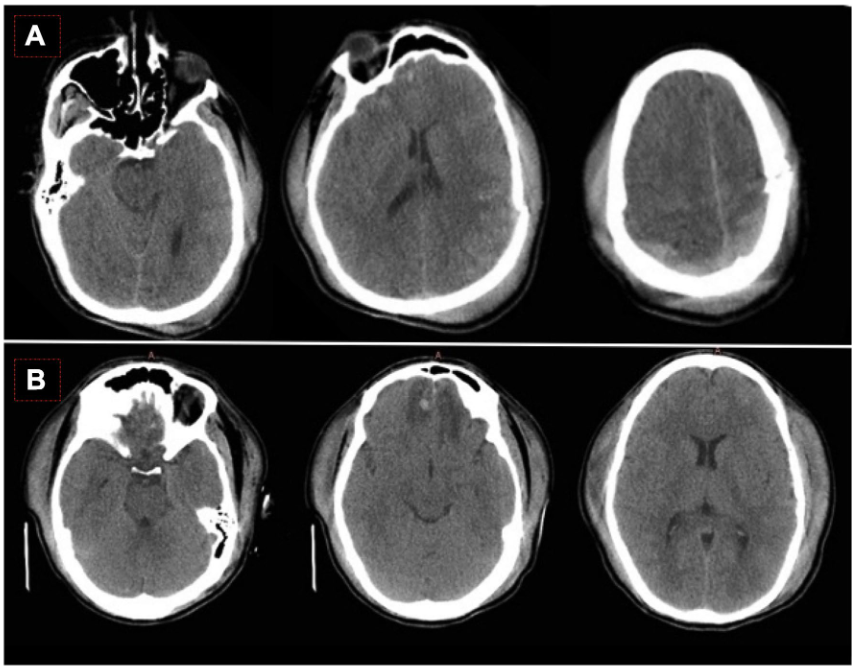

• • 一名20岁的男子遭受了攻击有关的孤立的头部外伤,GCS初始评分为12。初始头颅CT如图4a所示。6个小时后,他的病情恶化,GCS评分下降到7分,头颅CT示左侧颞部挫伤扩大。神经外科医生进行了血肿清除术和一侧去骨瓣减压术(图4b)。第2天,患者出现IH,采用分级措施(高渗盐水渗透治疗、中度过度通气、镇静和神经肌肉阻滞)进行控制。第2天头部CT扫描如图4c所示。第3天,患者出现难治性IH(ICP值为35-40mmHg,脑灌注压为70-75mmHg),对一级和二线治疗(消炎痛、CPP靶向治疗和巴比妥类药物)反应欠佳。图4d为第3天的头部CT扫描。由于CT上显示基底池未闭,我们在对侧(右侧)插入了另一个硬膜下ICP装置,并显示出相似的ICP值。置入腰大池引流管后颅内压得到控制,波动为10-12mmHg。该患者预后良好,GOSE评分为7分。

• 腰穿有什么用病例系列报道——使用控制性腰穿引流治疗基底池未闭的难治性颅内高压_https://www.jmylbn.com_新闻资讯_第5张

• 图4 案例6。a首次头颅CT。b第二次头颅CT(6h后):左侧颞叶挫伤和占位效应的扩大。c去骨瓣减压术后(第2天),当颅内压(ICP)用一级措施控制时,进行CT扫描。d 第3天的CT扫描,顽固性颅内高压和持续的基底池开放。置入腰大池外引流管后ICP得到控制。